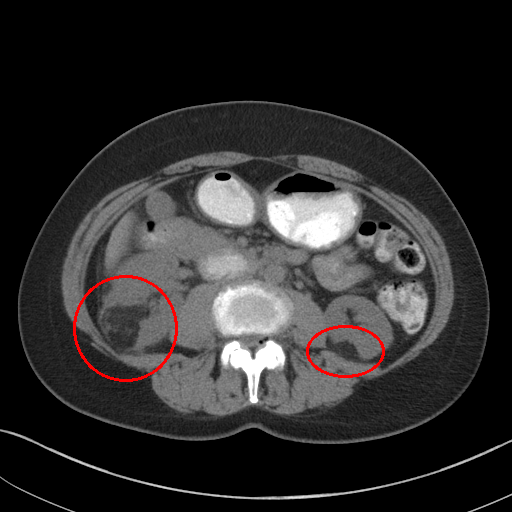

Figure 1: CT images under different window level and window width. (a) is the image used in 3DCE. (b),(c),(d) are the multi-view images used in our MVP-Net.

To accommodate for network input, previous studies [5, 6] use a significantly wide window222Windowing, also known as gray-level mapping, is used to change the appearance of the picture to highlight particular structures. to compress CT’s 12bit Hounsfield Uint (HU). However, this would severely deteriorate the visibility of lesions as a result of degenerated image contrast, as shown in Fig.1(a). In the clinical practice, fusing information from multiple windows are effective in improving the accuracy of detecting subtle lesions and reducing false positives (FPs). During visual inspection of the CT images, radiologists would combine complex information of different inner structures and tissues from multiple reconstructions under different window widths and window levels to locate possible lesions. To imitate this process, we propose to extract prominent features from three frequently examined window widths and window levels and capture complementary information across different windows with an attention based feature aggregation module.

The multi-view input for the MVP-Net is composed of multiple reconstructions under different window widths and window levels. Specifically, we adopt k-means algorithm to cluster the recommended windows (labeled by radiologists) in the DeepLesion dataset and obtain three most frequently inspected windows, whose window levels and window widths are [50,449]50449[50,449], [505,1980]5051980[-505,1980] and [446,1960]4461960[446,1960] respectively. As shown in Fig.1, these clustered windows approximately correspond to the soft-tissue window, lung window, and the union of bone, brain, and mediastinal windows respectively.

We also perform a case study to analyze the importance of multi-view modeling. As shown in Fig. 3, the model indeed benefits from the multi-view modeling: the lesions that are originally indistinguishable in the view of 3DCE due to the wide window range and lack of contrast, now becomes distinguishable under the view of appropriate windows. Thus our model presents better identification and localization performance.